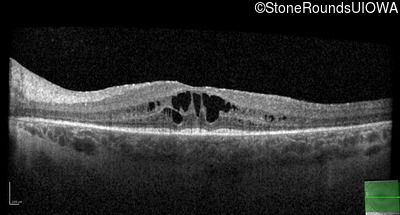

Optical Coherence Tomography - Right - 20/32 -1

Exemplar / OCT Stack

OCT Stack